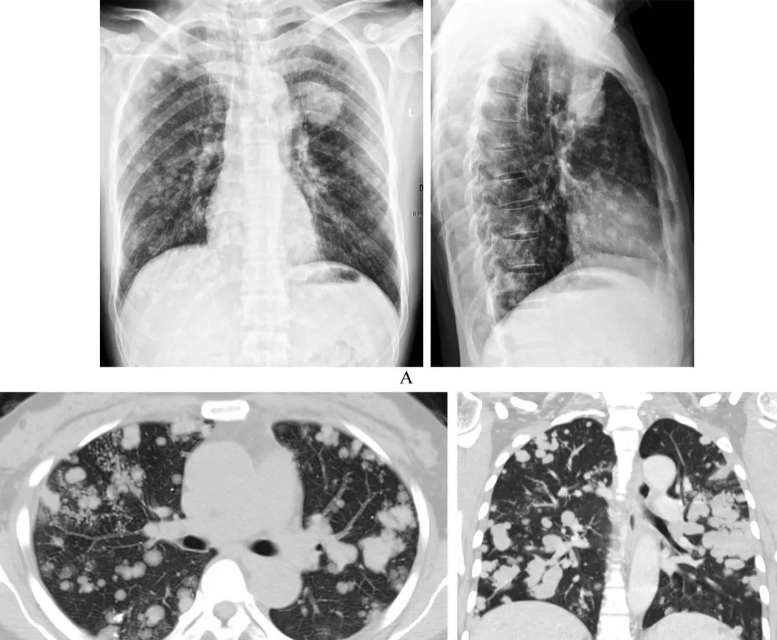

DTC发生肺部转移的胸部CT检查特征,主要分为(1)单发肺部结节(孤立);(2)多发肺小结节(直接≤1cm);(3)多发肺大结节;(4)双肺弥漫性转移灶。

单纯DTC肺部转移患者在接受碘131治疗的预后优于合并其他远处转移患者(骨、脑),单纯肺转移关心的10年生存率为73.6%。,而合并其他骨、脑转移的患者10年生存率低至34.3%。直径≤1cm的肺小结节转移患者的预后优于大结节(直径>1cm)肺转移患者,研究提出胸部CT没有肺转移(阴性)患者10年生存率达90.9%,小结节肺转移患者生存率为68.9%,而大结节肺转移患者仅为30.6%。(备注:数据来自2019年第八届中国医师协会外科医师分会甲状腺外科医师委员会官方报告数据)。